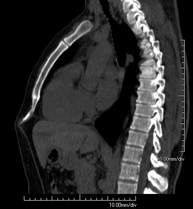

Prova diagnòstica no invasiva que consisteix en l'estudi de l'artèria aorta abdominal a través de l'obtenció d'imatges d'alta definició anatòmica mitjançant l'ús d'un equip de TC (Tomografia Computeritzada) i de contrast iodat. La qualitat de les imatges permet realitzar reconstruccions en 2D i 3D gràcies a estacions de treball especialitzades en l'estudi arterial. Està indicat en aquells pacients amb malaltia vascular (arteriosclerosi), en aneurismes d'aorta, en pacients amb dolor abdominal de possible origen vascular, en estudis prequirúrgics de lesions adjacents a l'aorta abdominal com a "mapa" vascular. La informació obtinguda de manera no invasiva és indispensable per als pacients que requereixen tractament percutani o quirúrgic. En aquells pacients que només requereixen seguiment de les lesions vasculars, aquesta tècnica és la tècnica no invasiva d'elecció juntament amb l'angio-RM. - Angio-TC Artèries renals

Prova diagnòstica no invasiva que consisteix en l'estudi de l'artèria aorta abdominal amb l'obtenció d'imatges d'alta definició anatòmica mitjançant l'ús d'un equip de TC (Tomografia Computaritzada) i contrast iodat. La qualitat de les imatges permet realitzar reconstruccions en 2D i 3D gràcies a estacions de treball especialitzades en l'estudi arterial. Està indicat en aquells pacients que pateixen malaltia vascular (arteriosclerosi), aneurismes d'aorta, en pacient amb dolor abdominal d'un possible origen vascular, en estudis prequirúrgics de lesions adjacents a l'aorta abdominal com el "mapa" vascular, etc. La informació obtinguda de forma no invasiva és indispensable per als pacients que requereixen tractament percutani o quirúrgic. En aquells pacients que només requereixen un seguiment de les lesions vasculars, aquesta tècnica és la tècnica no invasiva d'elecció juntament amb l'angio RM. - Angio TC d'artèries renals